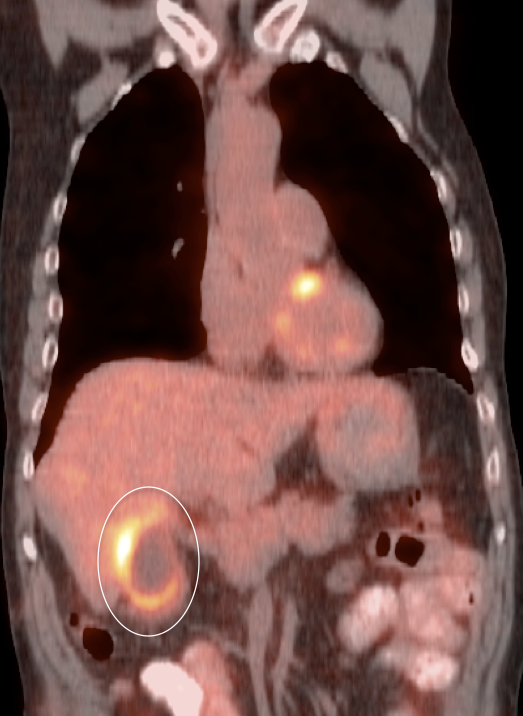

Gallbladder Cancer

Fast Facts:

- Most common biliary tract malignancy.

- Extremely lethal if symptomatic at presentation (mean survival ≈ 6 months).

- Associated with gallstones and chronic inflammation (incidentally found at surgery in ≈ 2% of routine cholecystectomy patients).

PET/CT Interpretation of Gallbladder Activity:

The normal gallbladder typically demonstrates little or no FDG uptake.

While focal intense gallbladder wall uptake can be seen with benign polyps, adenomyomatosis or focal inflammation associated with cholecystitis, malignancy must be excluded.

Initial Staging of Gallbladder Carcinoma:

- While PET/CT can detect the primary lesion, its true utility lies in the detection of regional nodes and distant metastatic disease.

- Distant Disease: Most commonly to the liver, lung and brain.